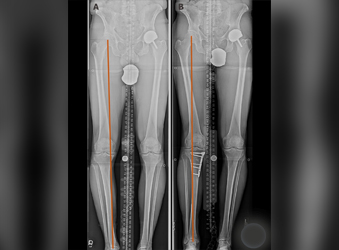

HTO (High Tibial Osteotomy) is a surgical procedure used to treat knee osteoarthritis by realigning the knee joint. Ilizarov is a type of external fixation device that is commonly...

Deformity correction using the Ilizarov method is a surgical procedure that involves the use of an external fixator to realign bones and joints in the body.

At Dr. Suhas Shah Orthopedic Center, we provide comprehensive orthopedic and trauma care under one roof, specializing in advanced techniques like Ilizarov surgery and limb lengthening & reconstruction. With over 16 years of experience, Dr. Suhas Shah has performed more than 1,400 Ilizarov surgeries and serves as a visiting Ilizarov specialist across Maharashtra.